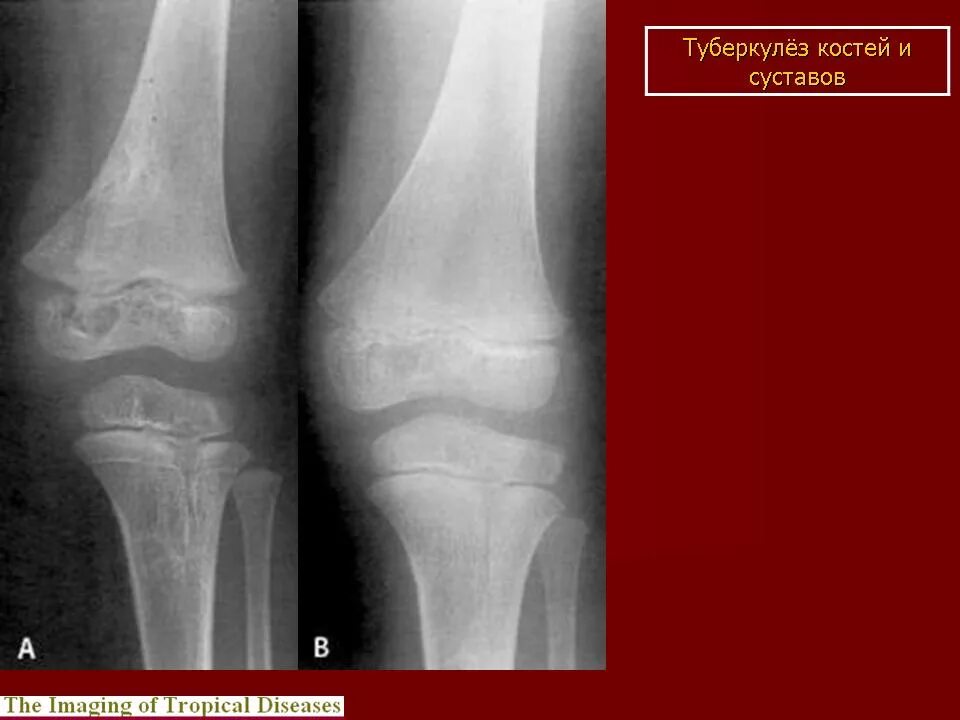

Туберкулез суставов симптомы